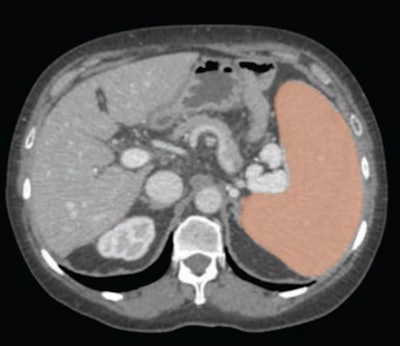

Estimating splenic volume has traditionally been done via linear measurements, but this approach has its limitations, according to Perez and colleagues. To explore assessing the spleen with volumetric analysis, the group conducted a study that included a screening cohort of 8,901 patients who underwent CT colonoscopy or renal-donor CT between April 2004 and January 2017. The team used a deep-learning algorithm that was developed, trained, and tested at the National Institutes of Health (NIH) Clinical Center to perform spleen segmentation and determine organ volumes; two radiologists reviewed these segmentations.

The team reported that the AI algorithm effectively calculated splenic volumes from CT exams in 8,853 patients from the primary cohort of 8,901 (99%), and that splenic volume had a statistically significant association with patient weight.